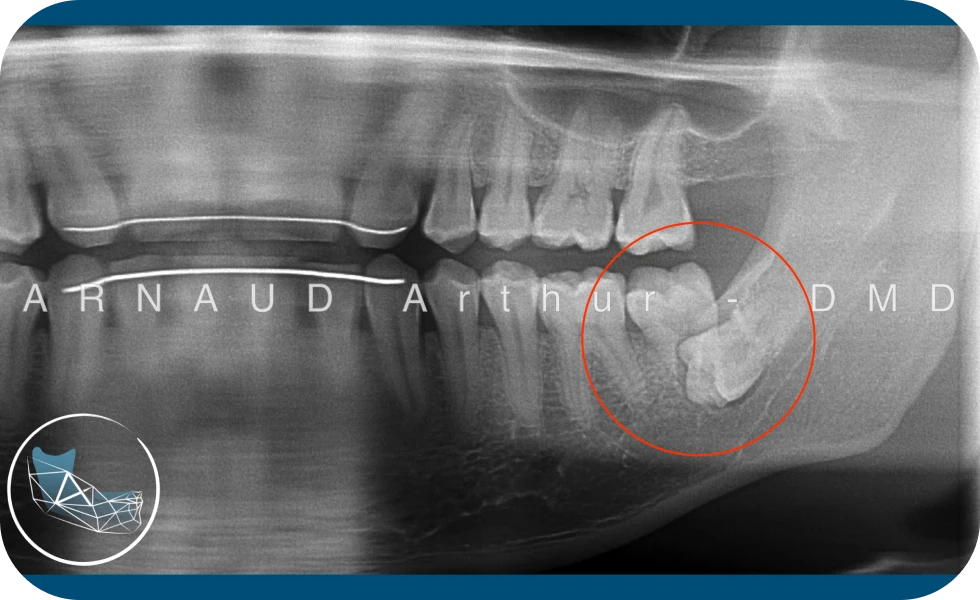

Dans la plupart des cas, il est recommandé de faire retirer les dents de sagesse avant que les dents ne soient complètement formées au niveau des racines. Les suites opératoires seront meilleures et les risques de complications qui peuvent survenir seront réduits.

Au fur et à mesure que les dents de sagesse se développent, les racines deviennent plus longues et l’os de la mâchoire plus dense.

Le moment idéal est chez certains patients, autour de 12 ou 13 ans et pour d’autres, ce ne sera peut-être qu’au début de la vingtaine.

Les problèmes ont tendance à survenir de plus en plus fréquemment aux alentours de 30 ans. Si vous ne savez pas si vos dents de sagesse doivent être retirées, contactez le Dr. Arnaud pour planifier une consultation.